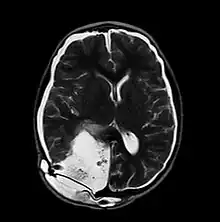

| MRI of Pseudomeningocele in 8 years old male patient | |

A pseudomeningocele is an abnormal collection of cerebrospinal fluid (CSF) that communicates with the CSF space around the brain or spinal cord. In contrast to a meningocele, in which the fluid is surrounded and confined by dura mater, in a pseudomeningocele, the fluid has no surrounding membrane, but is contained in a cavity within the soft tissues.